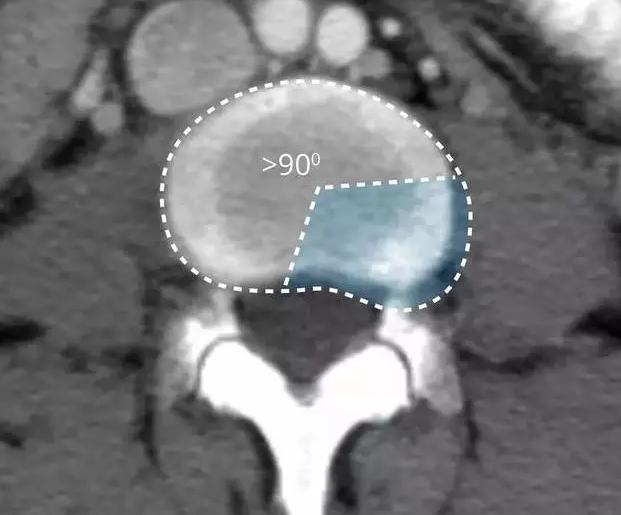

病情进一步进展,纤维环破裂了,髓核由于是胶状物在压力作用下就从破口处挤压了出来,这时候就是椎间盘的突出!

在影像学上表现为椎间盘局限性向椎管内突出。